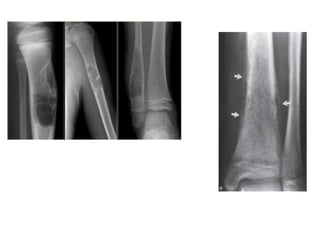

A : Geographic

B : Permeative

C : Moth eaten

Pattern of bone destruction •Geographic : destructive lesion with sharply defined border. Less aggressive, slow growing • Moth-eaten : area of destruction with ragged border. More rapid growth • Permeative : illed defined lesion with multiple worm holes. Spread through marrow space. Implied a aggressive malignancy

A : Geographic B: Permeative C : Moth eaten